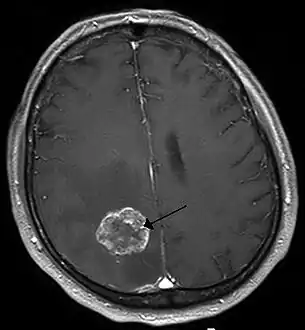

- Brain tumor

- Cavernoma